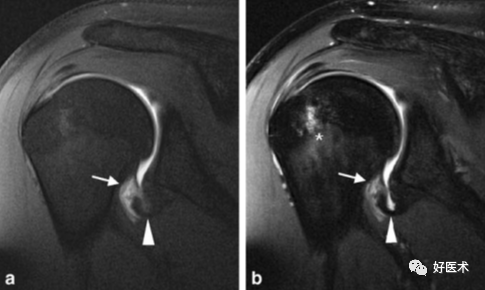

盂唇韧带复合体最佳显示体位(举过头顶并外旋、外展位)ABER position

上盂肱韧带、喙肱韧带、肱二头肌长头腱

ABER位(前臂外旋外展位):检出关节盂及韧带病变